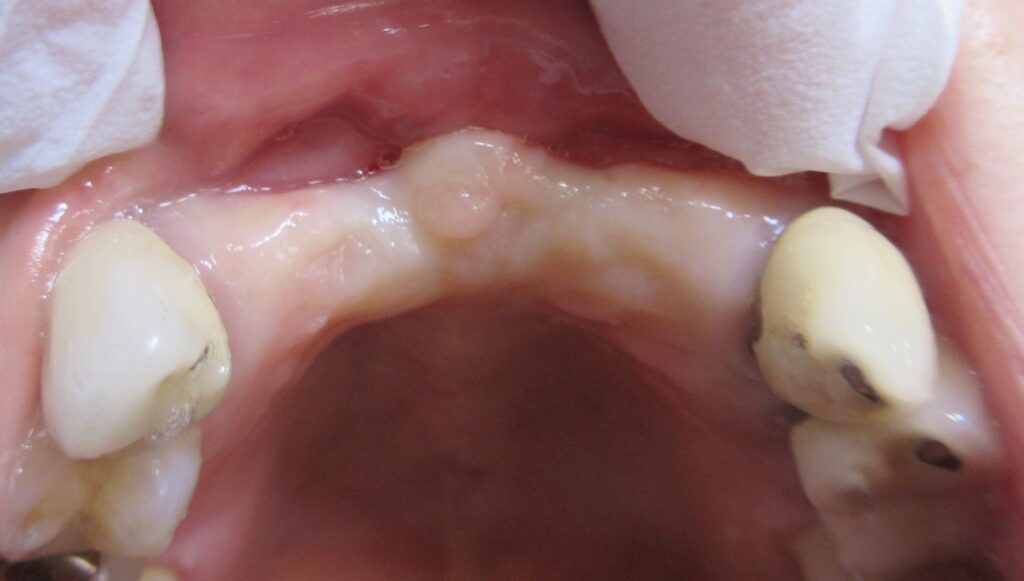

今回の患者様はインプラント植立を希望され、右上1番目・2番目、左上1番目・2番目の合計4本の植立が決まりました。

まずは左上1番目の歯茎から骨の部分までを穴開けパンチの要領で穴を開けていきます。

くりぬいた部分の歯肉を取り除き、次は骨に穴を開けていきます。

ドリルの先端を細い物から徐々に大きい物に変えながら、植立するインプラント体のネジの部分を除いた胴の部分の太さに合わせた大きさの穴を開けていきます。

開けた穴に、専用道具を使ってネジを締めるように長さ2センチ程のインプラントを骨に埋め込んでいきます。

続けて他の歯も同じように植立していきます。

インプラントオペでは、複数本を植立する場合でも、当時進行はせず、1本ずつ同じ工程を繰り返して植立します。

しっかりとインプラント埋め込まれた後は、動揺がないか、噛んだ時に当たらないかなどを確認して、最後にパノラマ写真を撮影して今回のオペは終了となりました。